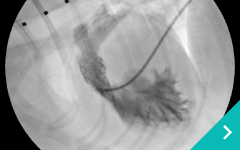

IVRとは、レントゲン透視(X線)や超音波などの画像を使いながら、カテーテルという細い管を体内に通して、病気のある部位を治療する方法です。開胸や開腹をせずに治療できることから、体への負担が少なく、多くのわんちゃん・ねこちゃんにとって優しい選択肢となります。

肝臓腫瘤に対する肝動脈塞栓術

肝臓腫瘤に対する

肝動脈塞栓術

脾動脈コイル塞栓術

脾動脈

コイル塞栓術

心臓カテーテル

心臓

カテーテル